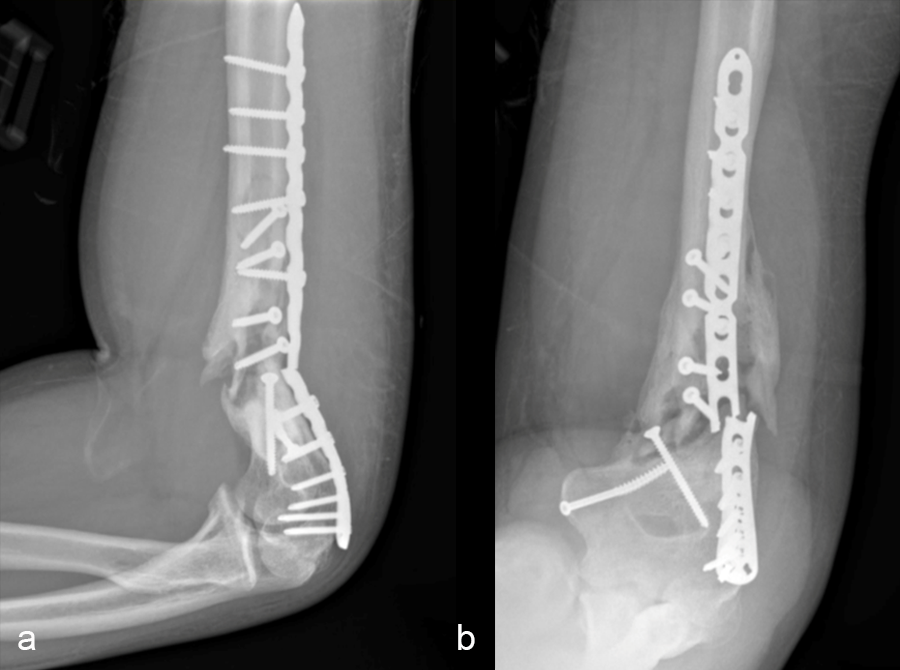

Case 2—Non-union/malunion of the distal humerus

(Case kindly provided by Brent Norris, Orthopedic and Trauma Services of Oklahoma, USA)

A 35 year-old male was admitted to the hospital in July 2022 with instability of the left elbow. He had a previous ORIF of the left distal humerus in January 2022 and no relevant medical history. He was positive for tobacco use (vaping).

Patient examination revealed a healed incision on the left upper extremity, with varus alignment of the elbow and an elbow range of motion of 90-120°. X-rays revealed a non-union/malunion of the distal humerus and implant failure (Fig 16).

In a first stage, the distal humerus was debrided and devitalized bone was resected, leaving an 8cm defect into which a cement spacer was placed. New plates were inserted to stabilize the fracture (Fig 17 and Fig 18). Cultures taken in the OR were negative.